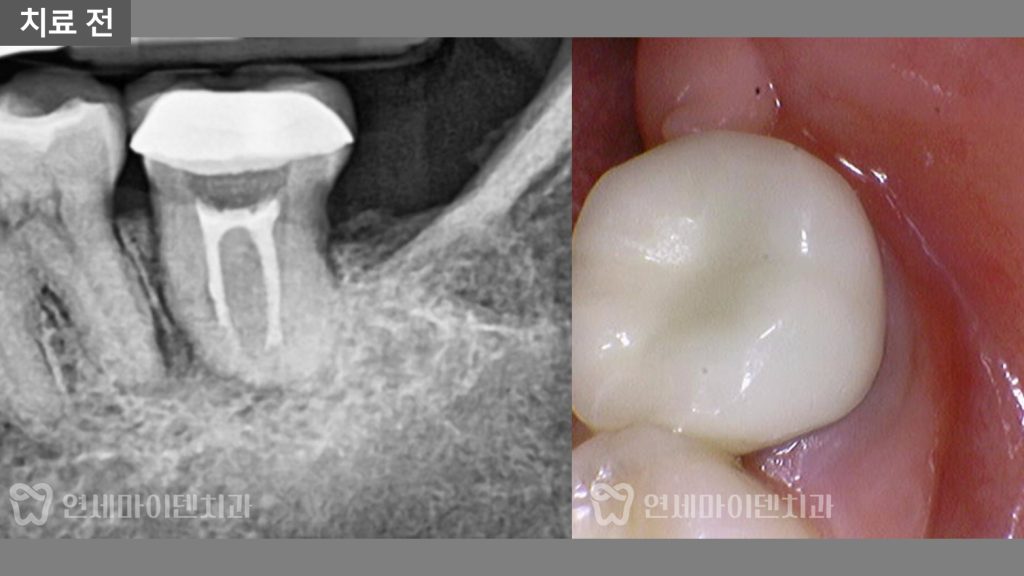

초진 시 잇몸 상태는 비교적 깨끗했고

뚜렷한 염증이나 붓기 소견은 보이지 않았습니다.

그럼에도 불구하고

씹을 때 불편감과 지속적인 통증이

남아 있는 상황이었습니다.

보철물 제거 후 확인된 실제 원인

원인을 정확히 확인하기 위해

기존 크라운과 레진 코어를 제거하고

치아 내부를 확인했습니다.

이 과정에서 예상하지 못한 재료가

내부에 남아 있는 것이 확인되었습니다.

신경치료 과정에서 임시 봉합용으로 사용하는

코튼롤(솜)이 제거되지 않은 채

치아 내부에 그대로 남아 있었던 것입니다.